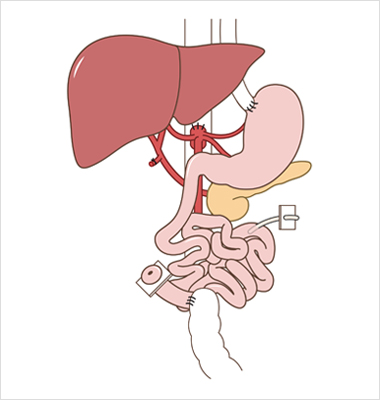

“장 자율성“ 을 획득하거나 경정맥영양으로 부터 독립하는 것

장부전 관리의 목표는 “장 자율성” 촉진을 통해 적절한 영양을 공급하고,

삶의 질을 개선하고, 이환율과 사망률을 낮추는 것